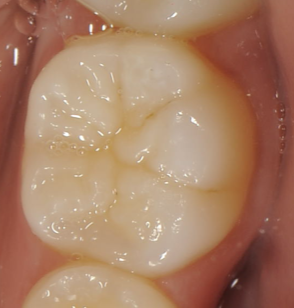

⬅️

虫歯になっていない奥歯